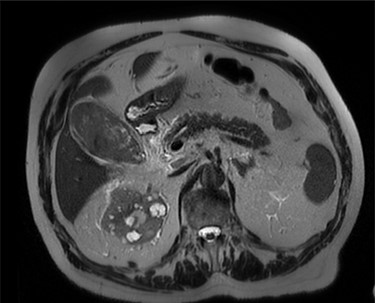

Intravenous broad-spectrum antibiotics were commenced, and the patient was admitted to the surgical ward and fasted for an MRI liver with gadolinium contrast. The MRI revealed no convincing features of malignancy; however, the gallbladder was distended with heterogeneous, predominantly low T1 and T2 content and demonstrating no internal enhancement, as seen in Fig. 2. These findings suggested the presence of sludge and/or luminal blood clod, and a further ultrasound (US) of the gallbladder was recommended. US scan, as shown in Fig. 3, confirmed cholecystitis with no evidence of cholelithiasis.

MRI scan of the patient, showing a distended gallbladder with low T1 and T2 content demonstrating no internal enhancement.